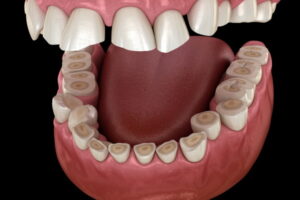

Tooth Wearとは、非細菌性で慢性的に進行する歯の硬組織欠損の総称です。

硬組織とは、歯の表面を覆うエナメル質や、その内側の象牙質、さらに歯の根元を覆うセメント質を指します。

これらの組織が、物理的な摩擦や化学的な腐食などによって徐々に失われていく状態がTooth Wearです。

Tooth Wearには、くさび状欠損、咬耗症、摩耗症、酸蝕症といった分類があります。